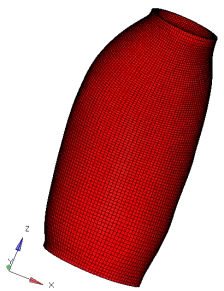

Abdominal Aortic Aneurysm (AAA) is an enlargement in the lower part of the main artery Aorta by 1.5 times its normal diameter. AAA can cause death if rupture occurs. Elective surgeries are recommended to prevent rupture based on geometrical measurements of AAA diameter and diameter growth rate. Reliability of these geometric parameters to predict the AAA rupture risk has been questioned, and biomechanical assessment has been proposed to distinguish between patients with high and low risk of rupture. Stress in aneurysm wall is the main variable of interest in such assessment. Most studies use finite element method to compute AAA stress. This requires discretising patient-specific geometry (aneurysm wall and intraluminal thrombus ILT) into finite elements/meshes. Tetrahedral elements are most commonly used as they can be generated in seemingly automated and effortless way. In practice, however, due to complex aneurysm geometry, the process tends to require time consuming mesh optimisation to ensure sufficiently high quality of tetrahedral elements. Furthermore, ensuring solution convergence requires large number of tetrahedral elements, which leads to long computation times. In this study, we focus on generation of hexahedral meshes as they are known to provide converged solution for smaller number of elements than tetrahedral meshes. Generation of hexahedral meshes for continua with complex/irregular geometry, such as aneurysms, requires analyst interaction. We propose a procedure for generating high quality patient-specific hexahedral discretisation of aneurysm wall using the algorithms available in commercial software package for mesh generation. For aneurysm cases, we demonstrate that the procedure facilitates patient-specific mesh generation within timeframe consistent with clinical workflow constraints while requiring only limited input from the analyst.